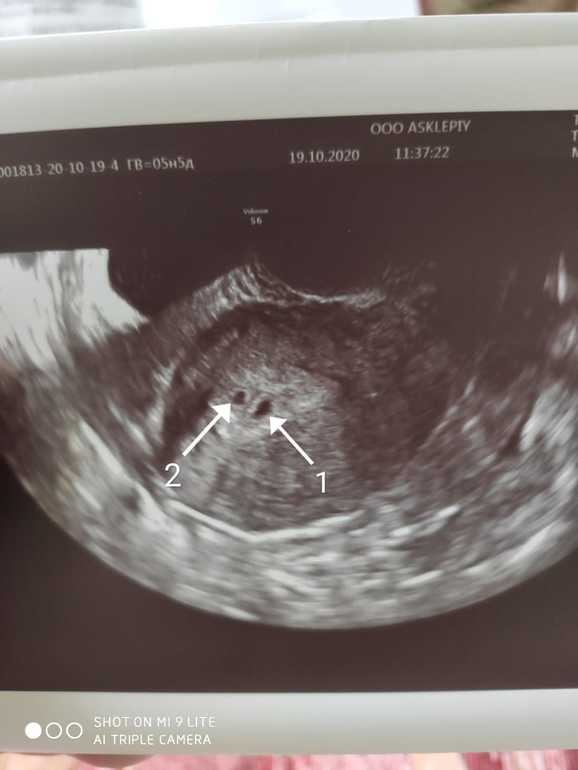

Я вот только родила двойню) динамику по тестам гляньте в дневнике моем) рано заполосктились, хгч рос в 4 раза быстрее обычного, на первом узи увидели 1пя, потом в 6 недель уже 2 увидели и 2 сердечка ) Удачи вам!

У меня была двойня, только на втором узи в 9 недель это было понятно, но один замер на сроке 6ти недель. По узи 6+2 видели только одного...